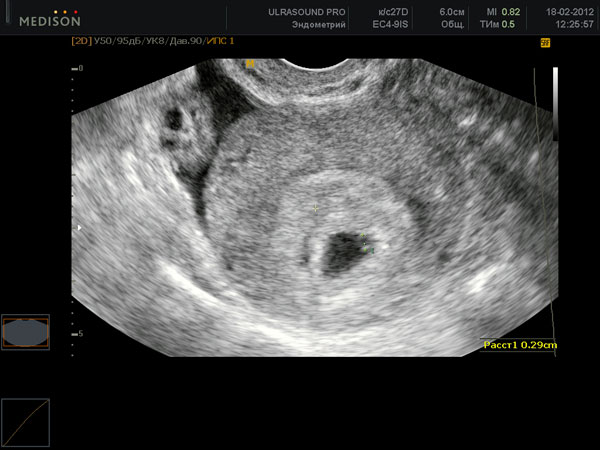

УЗИ на 4 неделе беременности

К концу четвертой недели беременности размеры зародыша составляют примерно 54 мм. Его в принципе можно увидеть с помощью высокоточного аппарата УЗИ, однако обычно эта процедура на таком раннем сроке не назначается, ведь многие женщины даже не подозревают о наступившей беременности.